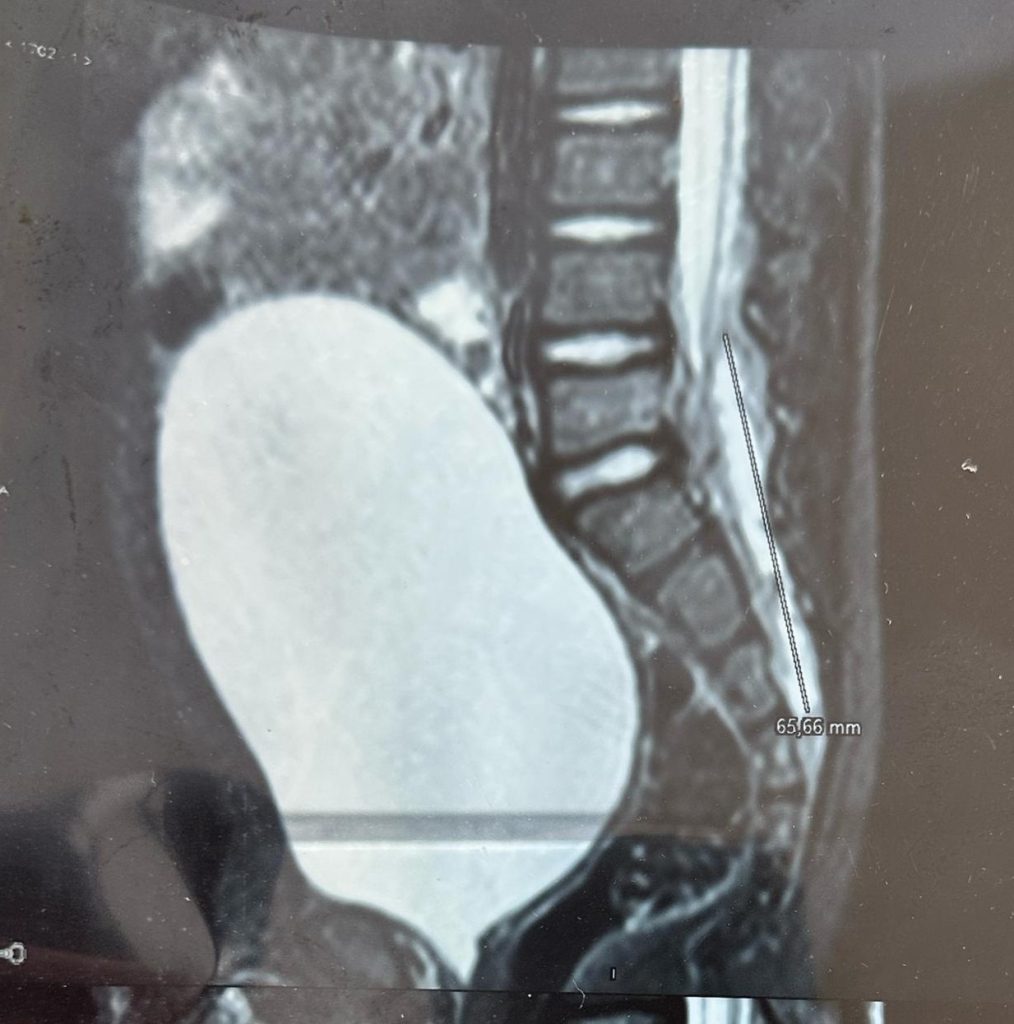

— “Na verdade, eu não tinha visto o nome nem a idade. Achei que estava analisando o exame de um idoso”, compartilhou Heverton, por conta de sua articulação destruída.

No fim daquele processo, ele havia sobrecarregado tanto o joelho esquerdo, já lesionado anos antes, que agora sofria com dores severas nos dois lados. Ainda assim, recusava-se a aceitar aquele diagnóstico. Amava se exercitar — tanto pela profissão quanto pelo estilo de vida — e não admitia viver limitado, tampouco acolher palavras de derrota. Ele cria que Deus não o havia chamado para viver daquela forma.